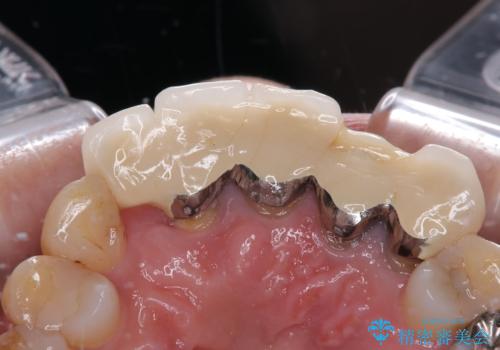

受け口を無理やりブリッジで改善したことで、支台歯の1本は歯根が破折しており抜歯が必要な状態でした。

根管治療がされている歯の一部には根尖部の違和感があり、根管治療が必要と判断されました。

抜歯および根管治療を実施した後にオールセラミッククラウンにて補綴することとしました。